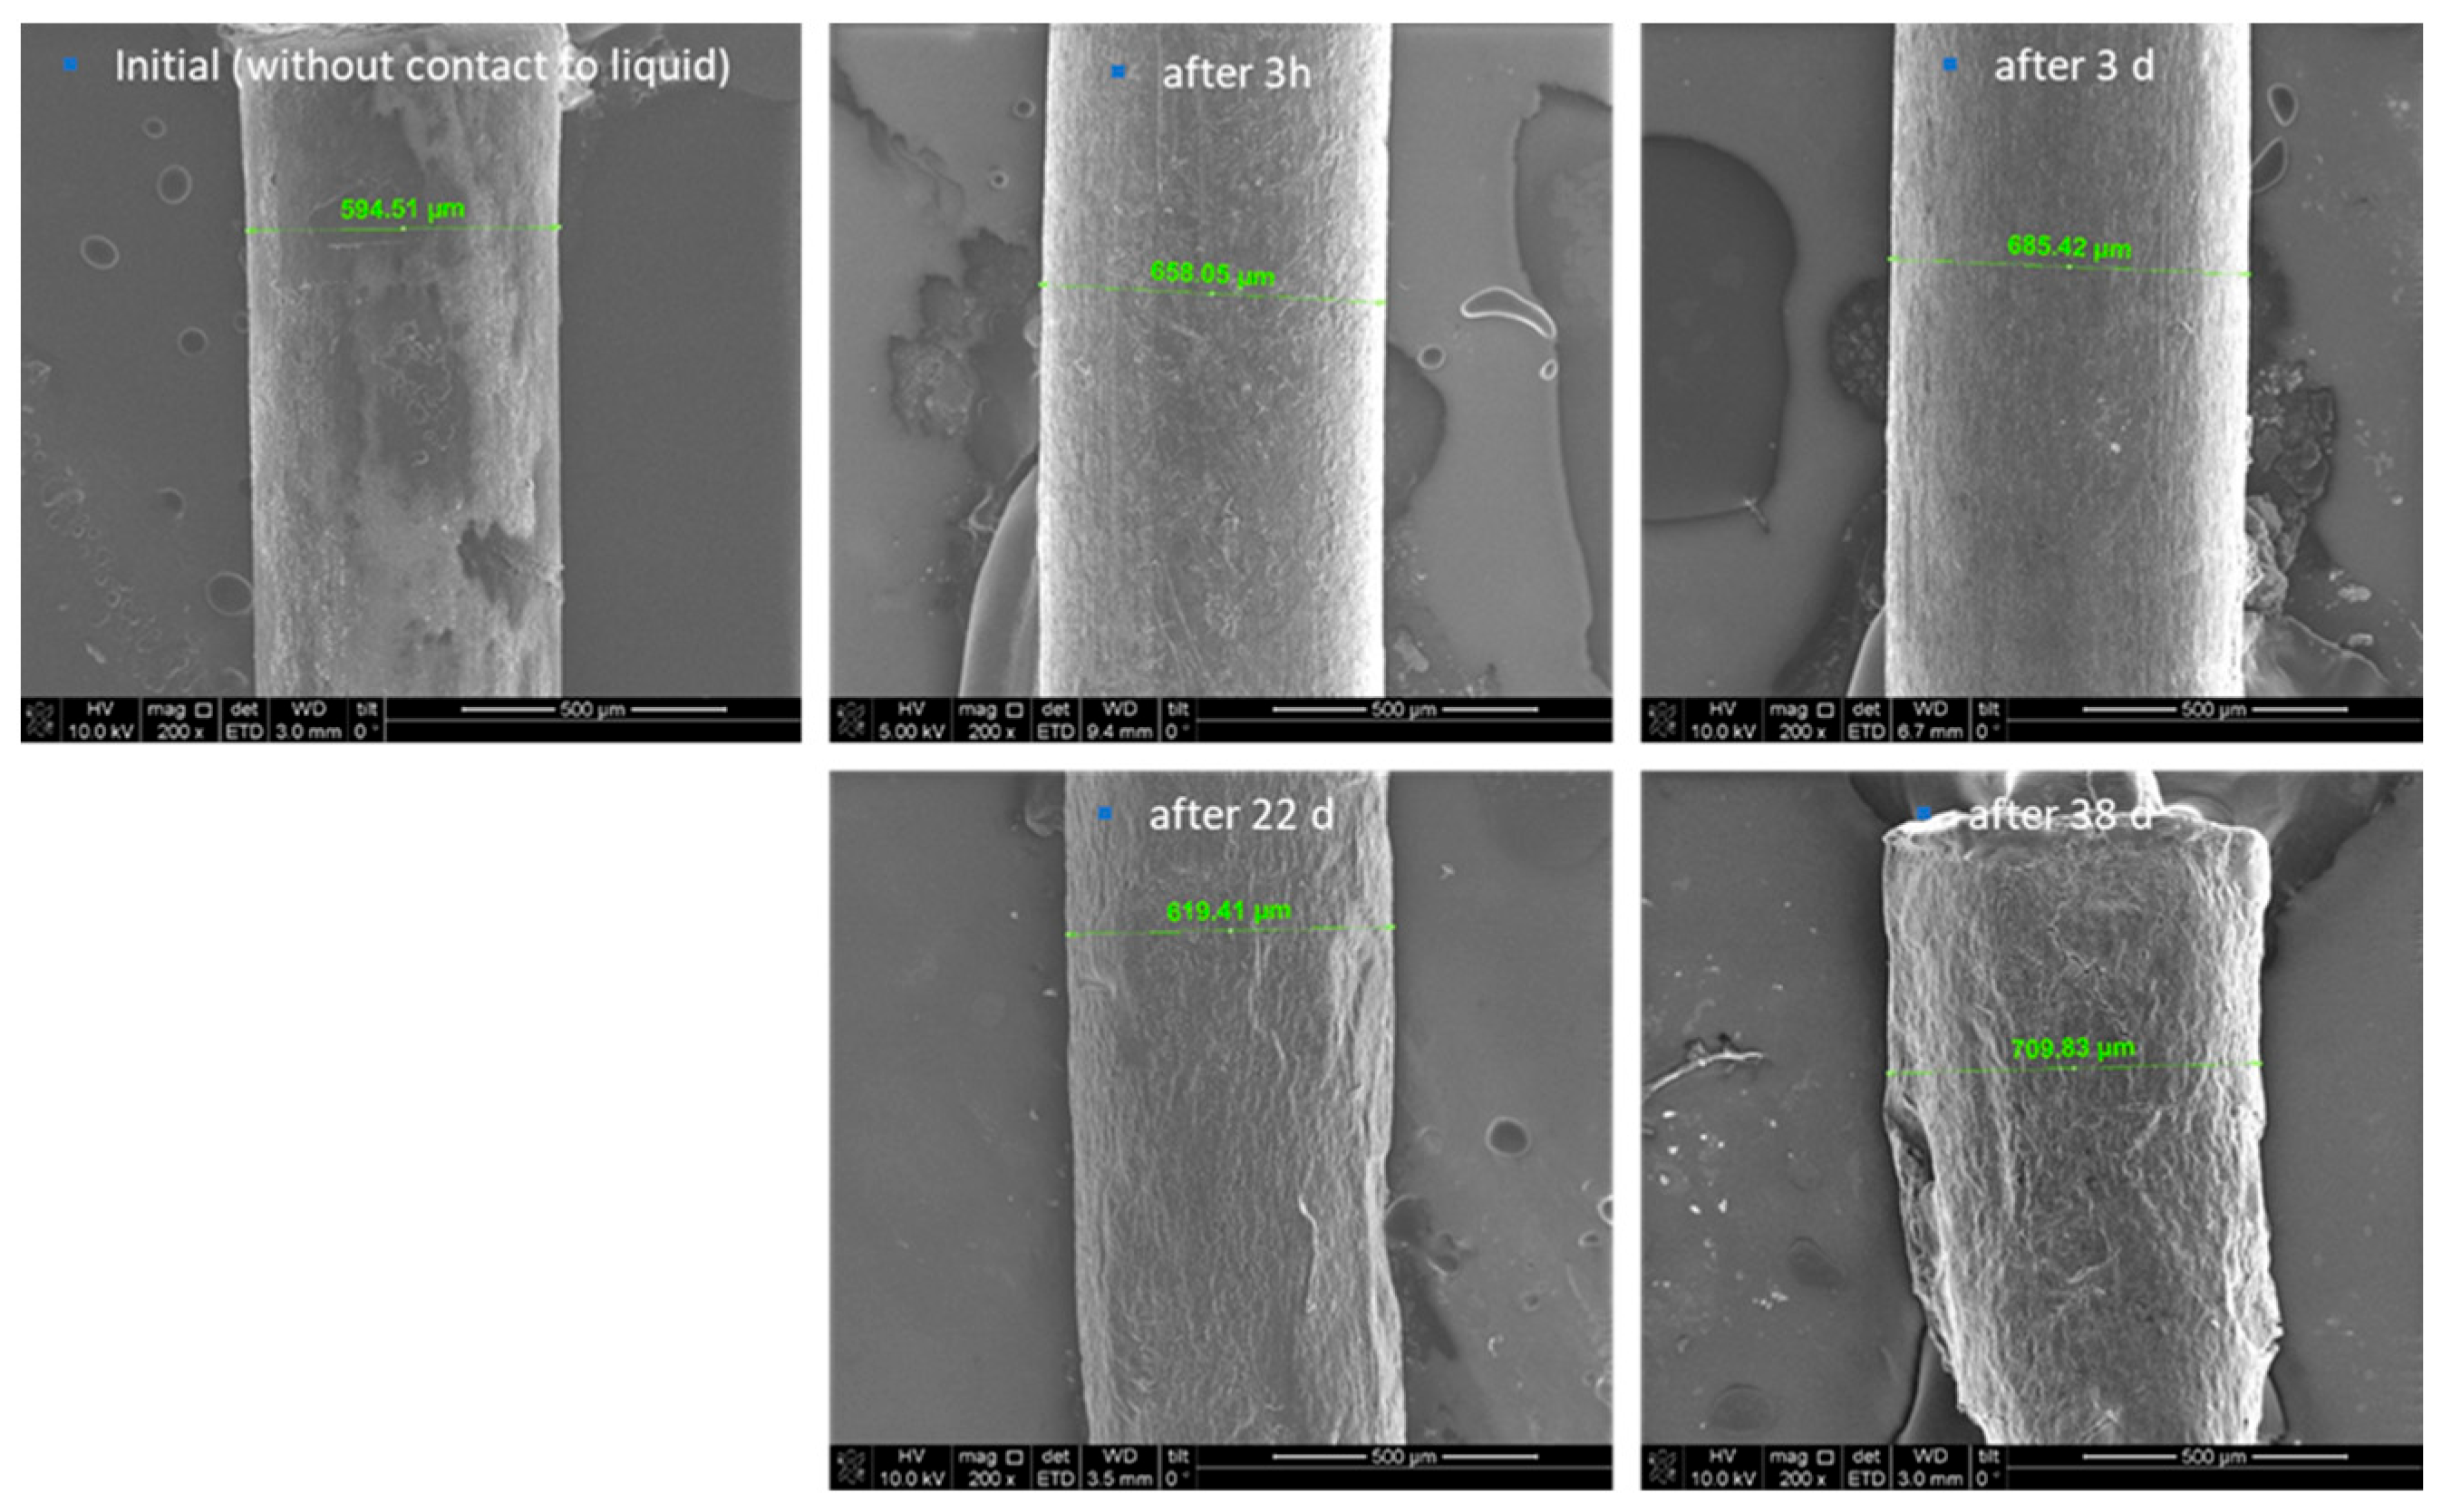

Furthermore, scanning electron microscopy (SEM) images were depicted and used for the description of the degradation behaviour of the formulation. Thereby, the initial state of the formulation is characterized by an inhomogeneous, partly rough surface (Figure 2). Structures with crystallite-like shapes are clearly visible. This finding can be explained by the included magnesium stearate of the MLC, which is known to form such surface structures. Again, an increase in the thickness of the thread and thus a clear swelling was determined after 3 h and 3 days in PBS. Even after 22 days, the thread diameter was still larger compared to the initial situation, however smaller than after 3 days. A possible explanation might be, that fragments start to detach from the surface, which is underlined by the detection of small amounts of magnesium stearate in the daily exchanged PBS. The ongoing degradation results in the formation of very small pieces, so after day 38 it was not possible to generate samples for further investigation of the process.

Further, the surface morphology of the extrudates was documented before, after 3 hours, and 3, 22 and 38 days by SEM (Quanta 3D FEG from FEI company). One sample was taken out at each time point from the PBS buffer and immediately prepared for the investigation using SEM analysis. Samples were prepared using the Nanosuit technology (NanoSuit® from NanoSuit Inc.) to obtain a conductive layer on the surface. The following magnifications were used: 200x and 10000x.

Figure 2. SEM images of the extrudates before, after 3h, 3d, 22d and 38d storage in PBS, 200x magnification.